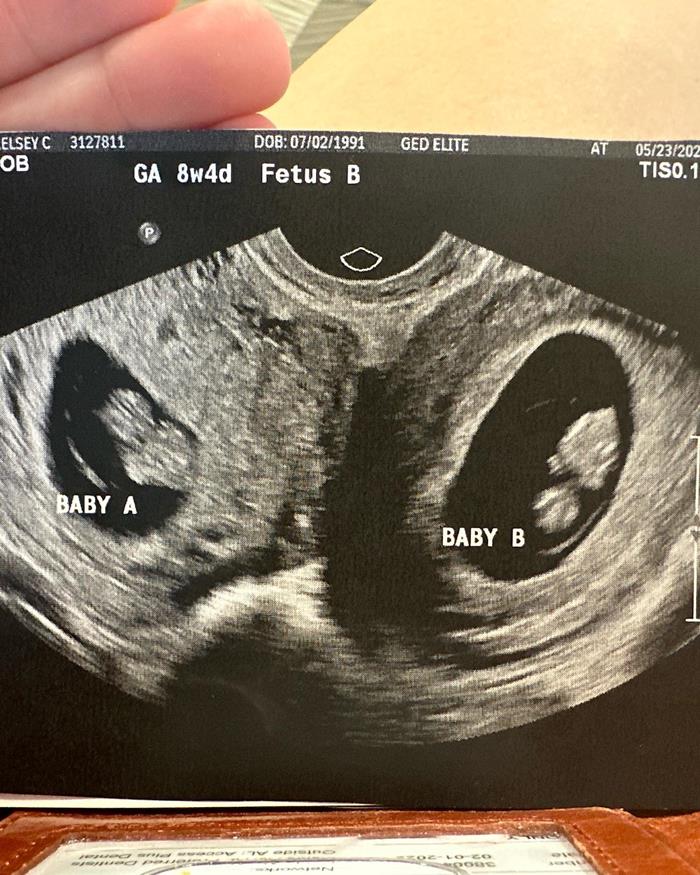

เคลซีย์เผยภาพอัลตราซาวด์ที่น่าทึ่ง แสดงให้เห็นชัดว่าเธอมีมดลูก 2 มดลูก และภายในนั้นก็มีทารก 2 คนอยู่แยกกัน โดยทั้งคู่เป็นเพศหญิง และเมื่อเร็ว ๆ นี้เธอได้ผ่านการตรวจประเมินสุขภาพของทารกในครรภ์และพบว่า ทารกทั้ง 2 ครรภ์มีสุขภาพแข็งแรง "ใบหน้าเล็ก ๆ ของพวกเขาน่ารักไหม ? คิดว่าจะคล้ายกันไหม ? ฉันรู้สึกว่าพวกเขาจะแตกต่างกันอย่างสิ้นเชิง" เคลซีย์ กล่าว